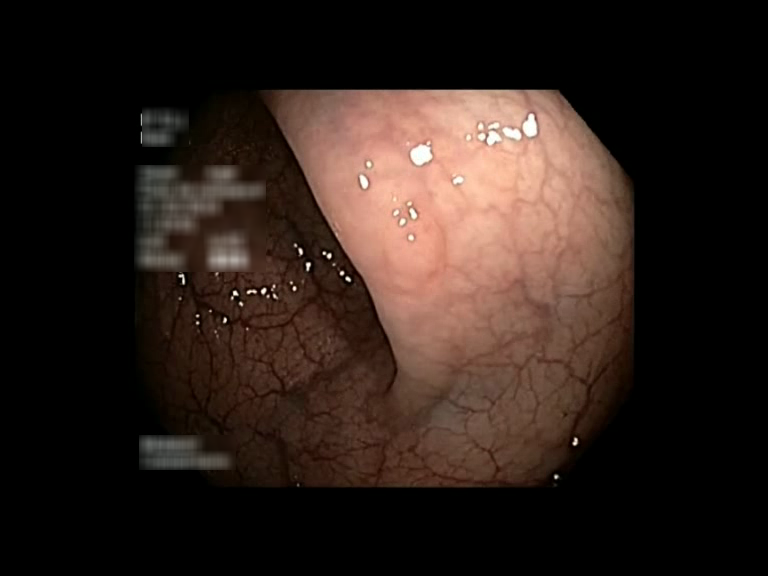

| Lesion | White Light Frame | NBI Frame | White Light Video | NBI Video | Camera Calibration |

| serrated_01 |  |

|

WL.mp4 | NBI.mp4 | cam.xml |